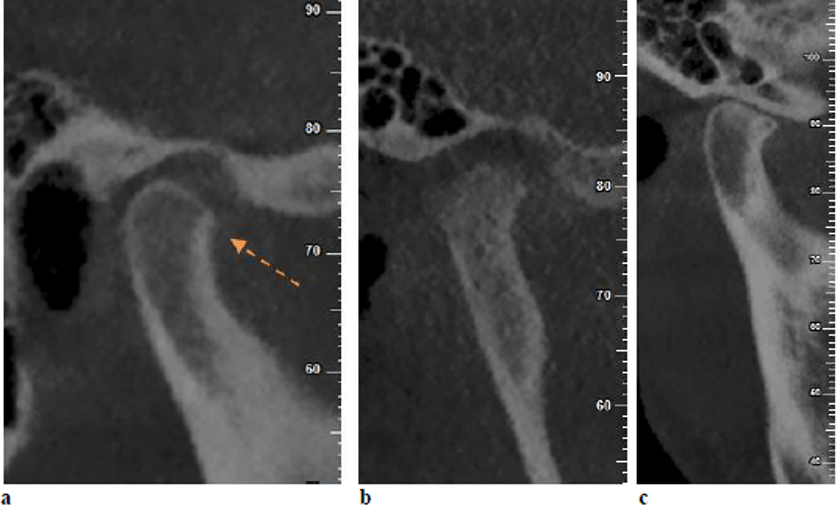

Estudios previos han informado que varios pacientes con trastornos de la ATM podrían sufrir cambios anatómicos en los tejidos óseos y/o blandos de la articulación temporomandibular. La anatomía de la ATM podría evaluarse mediante diversas técnicas, entre ellas la radiografía panorámica, la radiografía transcraneal, la tomografía computarizada de cone beam (TCCB) y la resonancia magnética (RM). La TCCB es una modalidad fiable para la evaluación de los defectos óseos de la ATM y esta es comparable a la tomografía computarizada (TC) en cuanto a precisión. Las imágenes de la ATM obtenidas mediante TCCB pueden proporcionar mucha información sobre los cambios óseos, incluyendo osteofitos, erosión, aplanamiento, esclerosis del hueso subcondral, anquilosis y seudoquistes.

En cuanto a los cambios óseos, no se encontraron diferencias significativas entre los pacientes con disfunción temporomandibular y los grupos asintomáticos en el presente estudio, que utilizó CBCT como herramienta de diagnóstico. Este hallazgo podría poner de relieve que las manifestaciones clínicas de los trastornos de la ATM muestran una escasa correspondencia con las alteraciones internas identificadas en las imágenes radiográficas. En consonancia con este hallazgo, Petersson, en un estudio de revisión, afirmó que los hallazgos radiológicos de la ATM podrían no correlacionarse constantemente con los hallazgos clínicos en pacientes con trastornos de la ATM. Además, Palconet informo de una escasa correlación entre los cambios estructurales en las imágenes TCCB y los signos y síntomas clínicos en los trastornos de la ATM. Magnus, en una serie de radiografías panorámicas correspondientes a pacientes con trastornos de la ATM, informaron de hallazgos radiográficos clínicamente relevantes relacionados con la ATM en el 25 % de los casos, mientras que el 11 % mostró hallazgos radiográficos relevantes no relacionados con trastornos de la ATM. Por el contrario, Cevi-danes encontró los pacientes con sintomatología dolorosa en la ATM tenían una frecuencia significativamente mayor de cambios condilares degenerativos en comparación con los individuos asintomáticos.

Shahidi, S., Salehi, P., Abedi, P., Dehbozorgi, M., Hamedani, S., & Berahman, N. (2018). Comparison of the bony changes of TMJ in patients with and without TMD complaints using CBCT. Journal of Dentistry, 19(2), 142.